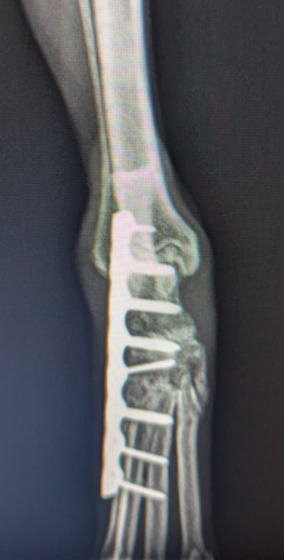

前十字靱帯断裂症例(2025/02/06)

HPの外科の前十字靱帯断裂のページに、犬のTPLO(脛骨高平部水平化骨切り術)手術を行った症例を追加致しました。大腿骨と脛骨を繋ぐ靱帯の一つである前十字靱帯が断裂すると、膝の関節が不安定となり関節炎が進行します。また膝関節内のクッションの役割を果たしている半月板にもダメージが加わり、痛みを生じて正常な歩行が出来なくなります。治療法としては術後の機能回復の早さから、近年ではTPLO法(脛骨の一部を円形に切り、角度を調整し膝関節を安定化させる手術)が多く選択されています。前十字靭帯断裂は中高齢犬によく見られる病気であり、膝蓋骨脱臼に併発することもあります。気になる症状がある場合はお早めにご相談下さい。

症例報告(2024/08/27)

外科の前十字靱帯断裂のページに、犬のTPLO(脛骨高平部水平化骨切り術)手術を行った症例を追加致しました。大腿骨と脛骨を繋ぐ靱帯の一つである前十字靱帯が断裂すると膝の関節が不安定となり関節炎が進行します。また、膝関節においてクッションの役割を果たしている半月板にもダメージが加わり、痛みを生じて正常な歩行が出来なくなります。治療として多くの場合手術が選択されますが、術後の回復の早さなどから近年ではTPLO法(脛骨の一部を切り角度を調整し膝関節を安定化させる手術)が多く選択されています。

犬のTPLO(脛骨高平部水平化骨切り術)手術(2024/08/07)

外科の前十字靱帯断裂のページに、犬のTPLO(脛骨高平部水平化骨切り術)手術を行った症例を追加致しました。大腿骨と脛骨を繋ぐ靱帯の一つである前十字靱帯は、断裂すると膝の関節が不安定となり関節炎が進行し、またクッションの役割を果たしている半月板にもダメージが加わることで、痛みを生じて正常な歩行が出来なくなります。治療として多くの場合手術が選択されますが、術後の回復の早さなどから近年ではTPLO法(脛骨の一部を切り角度を調整し膝関節を安定化させる手術)が多く選択されています。